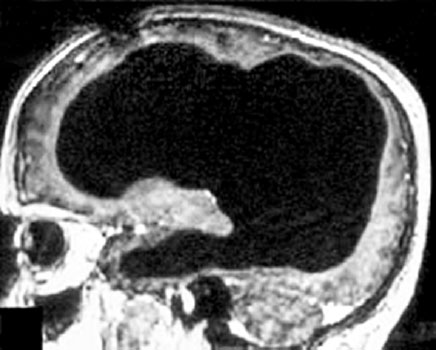

Пожалуй, наиболее известная иллюстрация – это история мужчины 44 лет, который прожил значительную часть своей взрослой жизни с 10 % мозга. На месте остальных 90 % была заполненная жидкостью полость, которая возникла из-за длившегося долгие годы отмирания нервной ткани. Тем не менее ни он, ни даже его близкие не подозревали об этом. Он вел вполне обыкновенную жизнь, имел жену, детей и постоянную работу на государственной службе.

МРТ-снимок мозга, демонстрирующий отсутствие около 90 % нервной ткани (сплошное затемнение). Черепная коробка мужчины в основном заполнена жидкостью.

Подробное описание его случая вместе с МРТ-снимками мозга было опубликовано в самом авторитетном медицинском журнале Европы Lancet в 2007 году и до сих пор поражает научное сообщество[11].